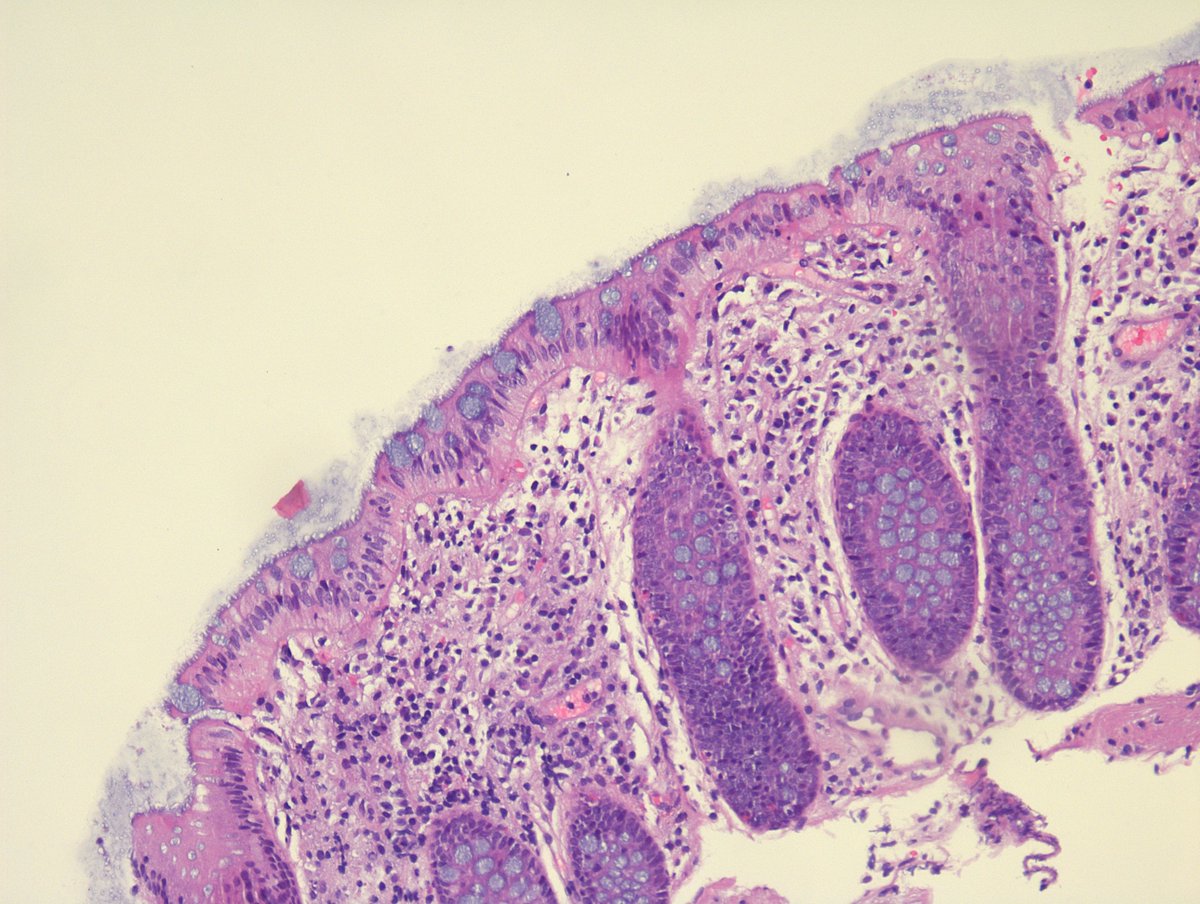

35 yo female with a thyroid neoplasm and extensive lymph node metastases. FNAC indicates Bethesda VI - PTC. What would you call it?

Annamária Ribiánszky, MD tweet mediaAnnamária Ribiánszky, MD tweet mediaAnnamária Ribiánszky, MD tweet mediaAnnamária Ribiánszky, MD tweet media